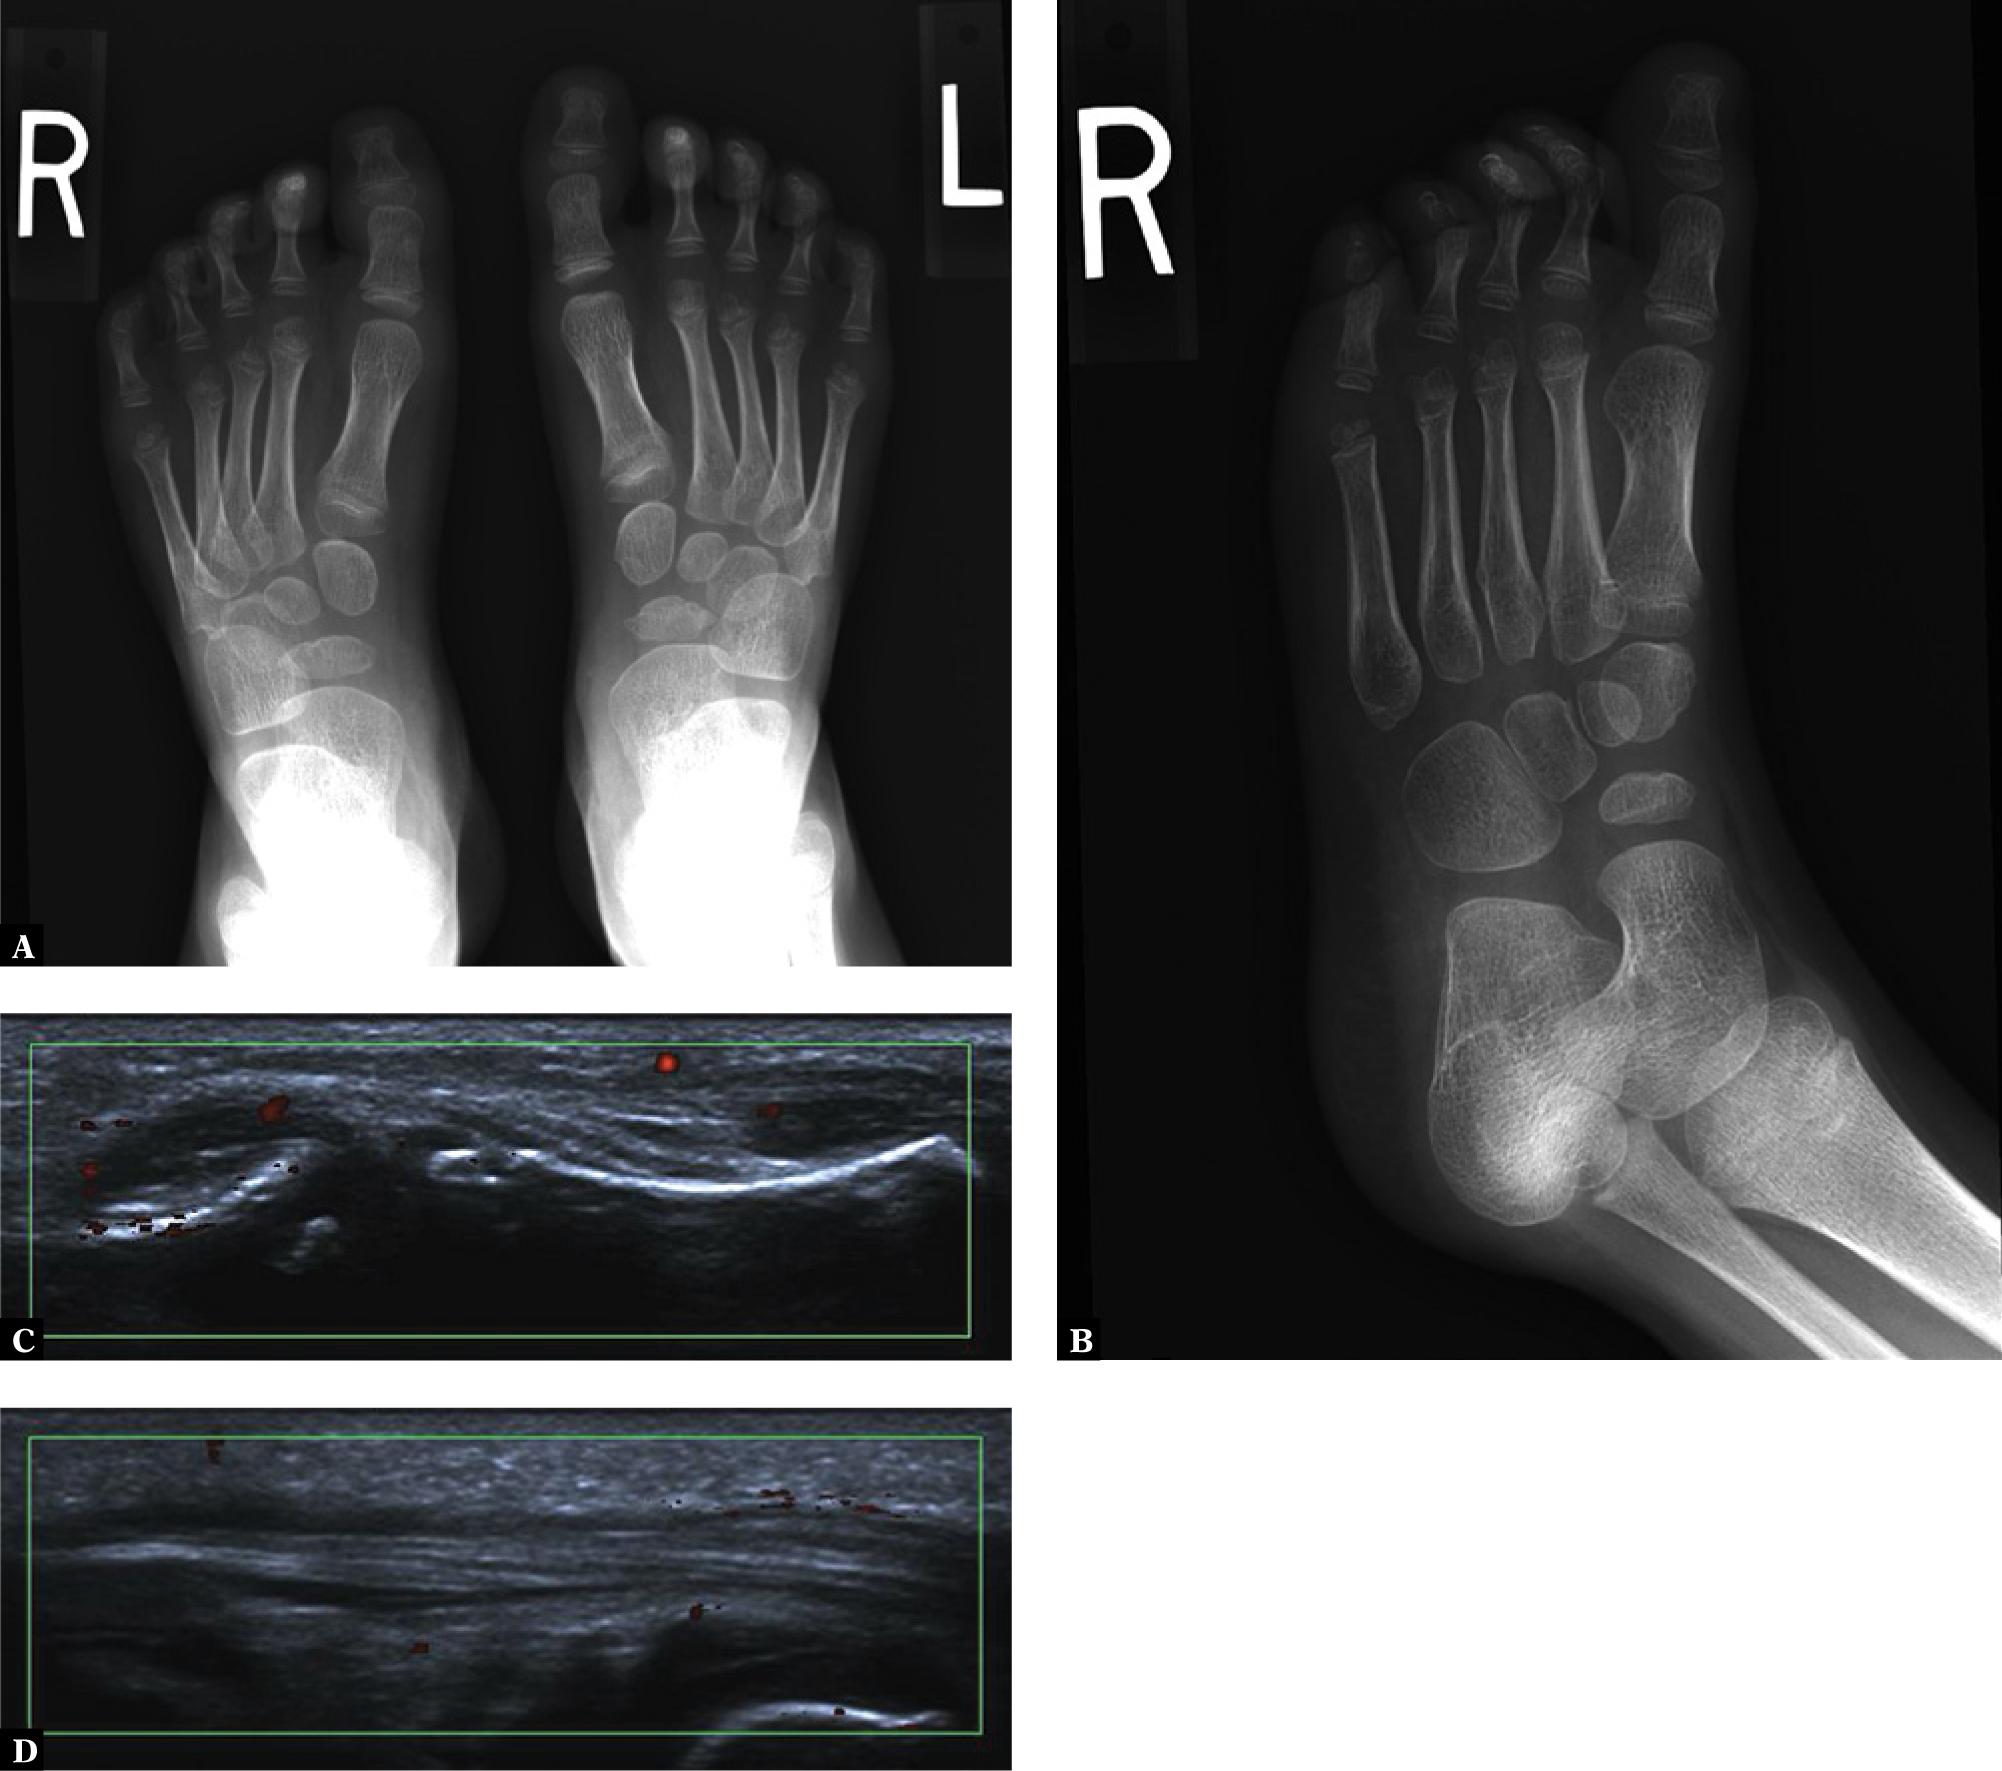

This form of juvenile SpA occurs in children sporadically. The features of this disease are the same as in adults(33). Frequently, eye inflammation is diagnosed. Asymmetrical oligo- or polyarthritis are seen most commonly, as in JPsA, with involvement of large joints of the lower limbs (knee and ankle, but rarely the hip). Sometimes foot dactylitis is seen (Fig. 6).

Right first toe synovitis and tenosynovitis in a 4-year-old girl: a feet AP radiograph (A) and an oblique view of the right foot (B) show increased density of periarticular soft tissues at the MTP1 and IP joints; ultrasound shows active synovitis at these 2 joints (C) and tenosynovitis of the FHL (D)

On radiographs, thickening and increased density of periarticular soft tissues of the affected joints is visible. Periarticular osteoporosis appears during an acute attack, but it could be absent in the chronic inflammation, or present only very discretely. Erosions are initially marginal, then subchondral, finally resulting in the narrowing of the joint spaces. US and MRI may show effusions, synovitis, and finally destructive lesions.

In comparison to adult patients with ReA, enthesopathy occurs infrequently, with the calcaneal tuberosity affected most commonly.